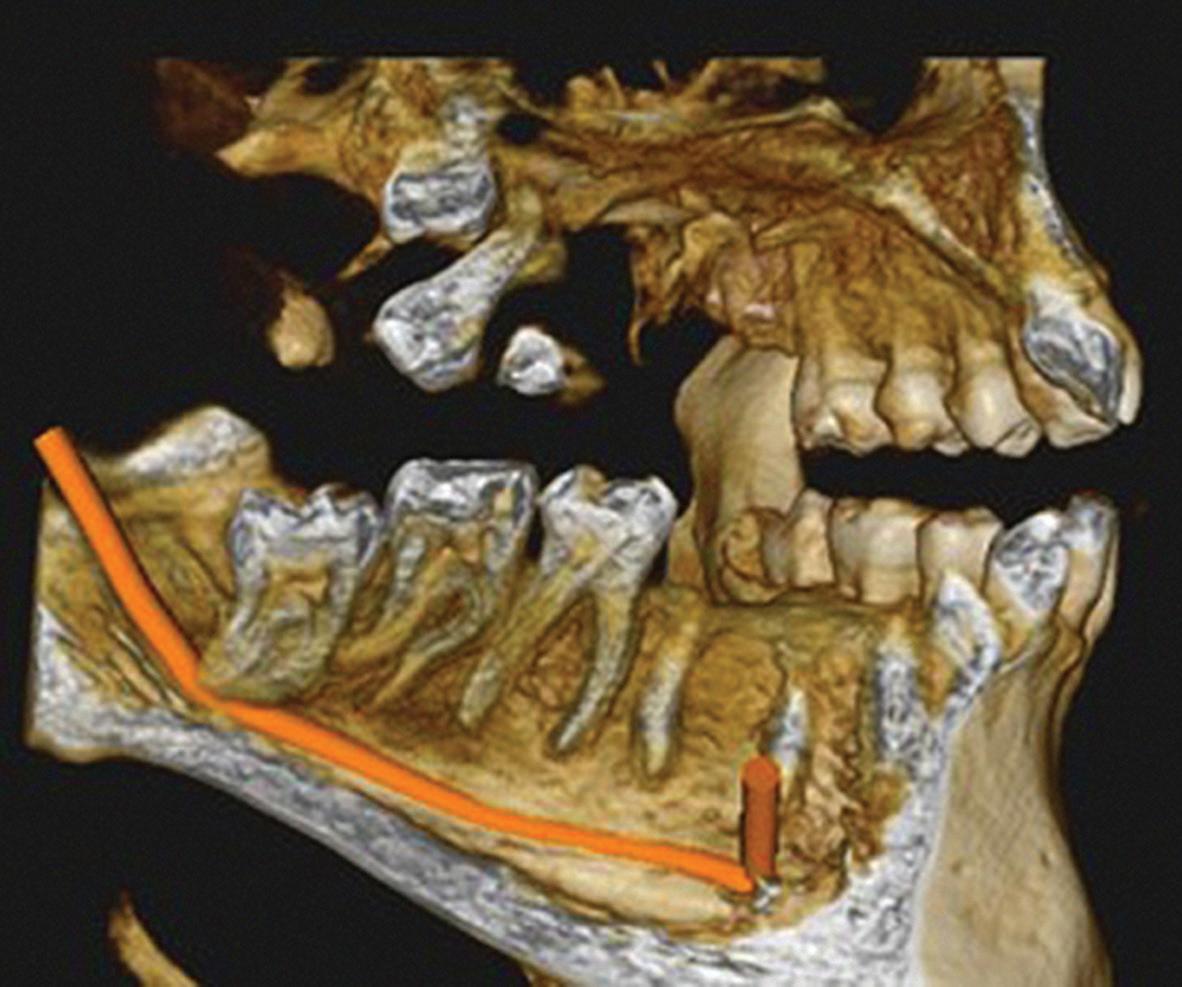

Figure 1: Radiographic Image of implants do not demonstrate bone loss due to the bisecting angle of the radiograph taken.

Figure 2: Radiographic image in a paralleling technique of implants dem onstrate moderate peri-implantitis with bone loss that will necessitate treatment.